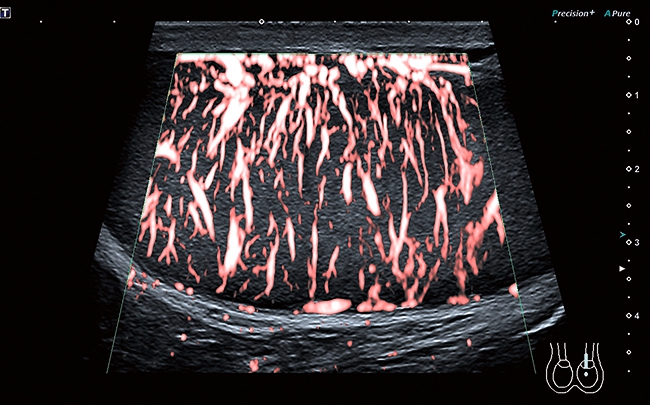

• Технология SMI для визуализации микроциркуляторного русла и отображения низкоскоростного кровотока в микрососудах

Функция получения трехмерного изображения в режиме цветового допплеровского картирования

Эта функция поможет вам получить качественные трехмерные цветные изображения при проведении исследования. Нужного эффекта удается достичь за счет использования датчиков 3D/4D в В-режиме с последующим восстановлением объемной структуры в режиме ЦДК. Кроме того, данная функция совместима с режимом Freehand 3D.

Цветной доплер

Эта функция поможет в исследованиях сердечно-сосудистой системы. Вы сможете выделить цветом характер кровотока на интересующем вас участке. Кровяной поток, идущий от датчика, отображается синим, к датчику – красным. Турбулентный поток фиксируется в сине-зелено-желтой цветовой гамме.